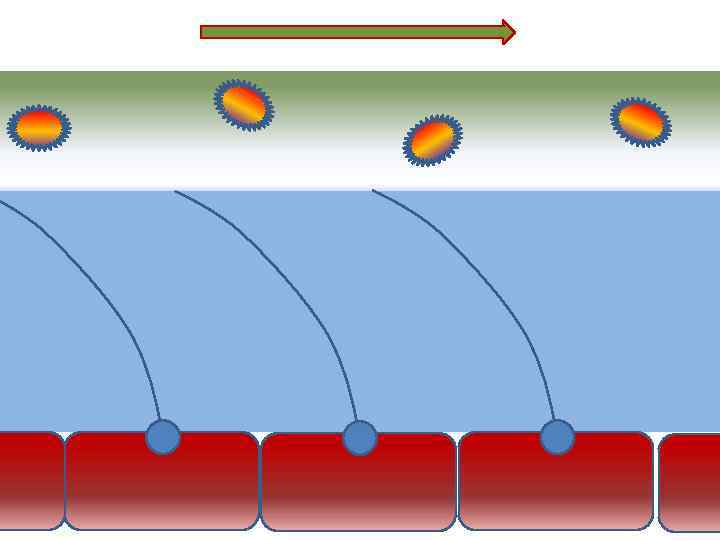

Факторы риска Недостаточное увлажнение дыхательной смеси ! Слизистая оболочка трахеи и бронхов обязательно должна быть укрыта секретом

Факторы риска Недостаточное увлажнение дыхательной смеси ! Слизистая оболочка трахеи и бронхов обязательно должна быть укрыта секретом

Факторы риска Недостаточное увлажнение дыхательной смеси • естественное удаление бактерий • состояние эпителия трахеи и бронхов

Факторы риска Недостаточное увлажнение дыхательной смеси • естественное удаление бактерий • состояние эпителия трахеи и бронхов

Оптимальное увлажнение 37°С, 44 мг/л Оптимальная влажность • Уменьшает время нахождения патогенной флоры в легком

Оптимальное увлажнение 37°С, 44 мг/л Оптимальная влажность • Уменьшает время нахождения патогенной флоры в легком

Механика движения воды из клеток вода П р о с в ет т р а х е и

Механика движения воды из клеток вода П р о с в ет т р а х е и

Движение клеток реснитчатого эпителия Движение вперед 1 – 3 Обратное движение 4 – 8

Движение клеток реснитчатого эпителия Движение вперед 1 – 3 Обратное движение 4 – 8

Оптимальное увлажнение Достаточная продукция слизи Хороший транспорт Экономит энергию и воду Защитная функция

Оптимальное увлажнение Достаточная продукция слизи Хороший транспорт Экономит энергию и воду Защитная функция

Механизм защиты легкого Слизь (зеленый цвет) нейтрализует и связывает патогенную флору(синий цвет) Слизь – это барьер между клетками и патогенной флорой Слизь – это транспортное средство

Механизм защиты легкого Слизь (зеленый цвет) нейтрализует и связывает патогенную флору(синий цвет) Слизь – это барьер между клетками и патогенной флорой Слизь – это транспортное средство